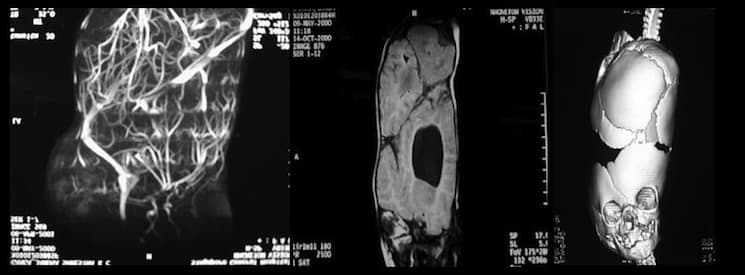

The venous architecture of craniopagus twins is extremely complex and highly intertwined, and the work of pumping all that blood is shared —sometimes unequally— between the two hearts. A detailed account of the separation procedure is documented in Goh (2004). In deciding if the twins could be separated, the multidisciplinary team of “neurosurgeons, plastic surgeons, anaesthetists, paediatricians, neurologists, a geneticist, dietician and physical, speech and occupational therapists” considered three main points: “(1) Were the brains separate? (2) Were the arterial and venous systems separate? (3) Could the resulting defect be closed?” Despite the daunting task of separating all of the vessels, the surgery is possible and the case presented ended successfully for both twins.